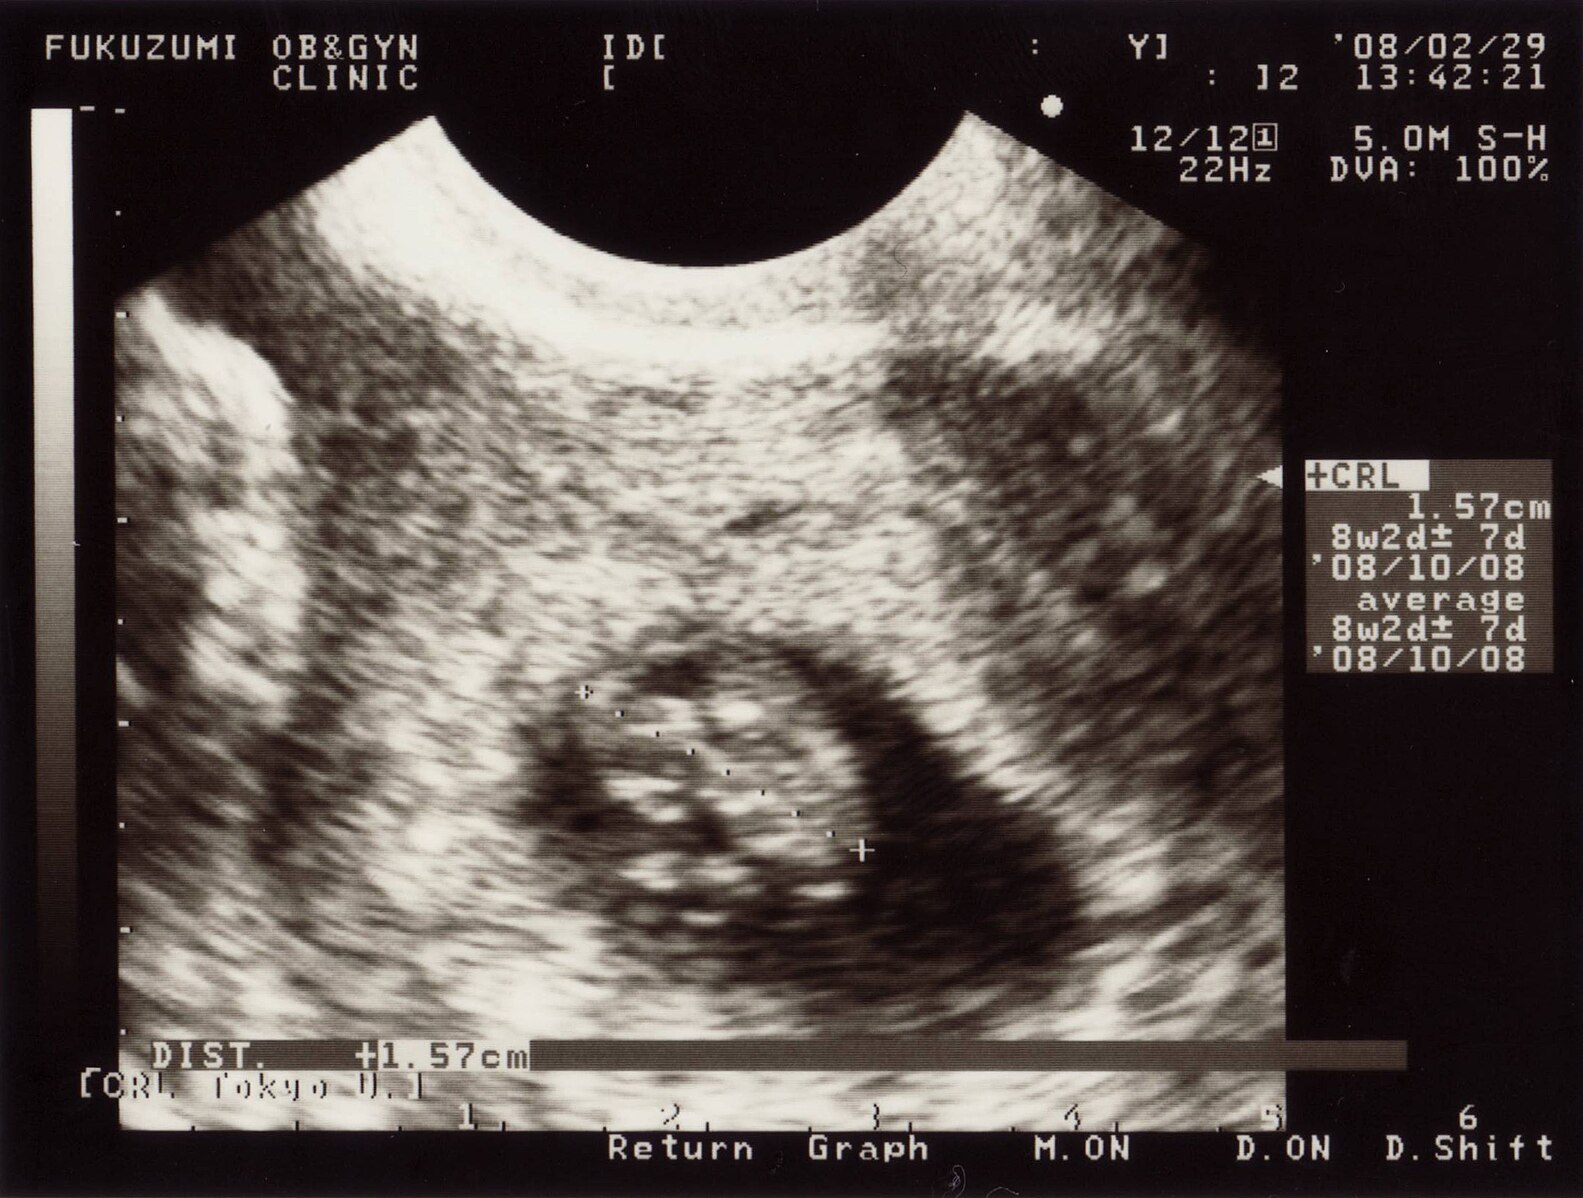

然后,它产下了一颗蛋。蛋壳是半透明的,我能隐约看见婴儿在里面蜷缩着的轮廓——小小的手,小小的脚,和B超里拍出来的一模一样。